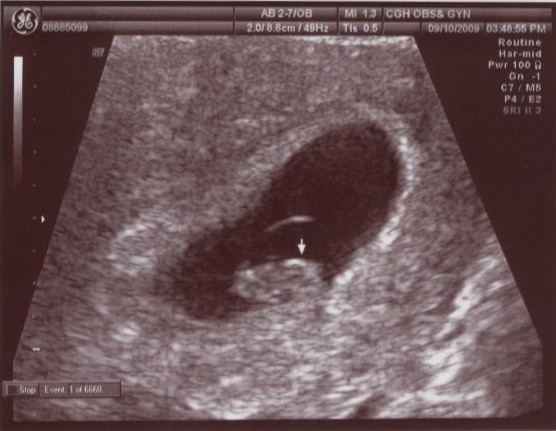

• 9月 10 週四 200920:09

• 7W5D 國泰產檢

7W4D.jpg

今天第一次到國泰產檢,心裡還挺擔心的,很怕遇到不合的醫生,這樣又要在去找其他的醫院,有點麻煩。

還好,蔡醫生人很不錯,而且我是平日去,也不用等太久,還幫我在做一次超音波,確認高小虎的大小。這次已經可以微微的看到形狀了,還有一閃一閃的心跳,真的很奇妙。高大爺要上班,大概也沒辦法陪我去做產檢,可是透過螢幕看到裡面的東西在動的時候,才會覺得,哇!!是一個生命ㄟ!